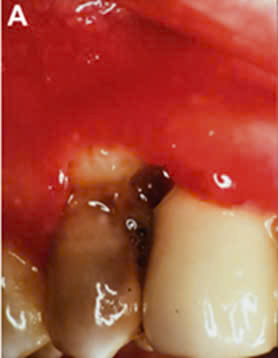

Hình 3: Xương ổ răng bị tiêu, lợi bị hoại tử ở vùng răng 13-14.

Hình 4: Xương ổ răng và nhú lợi vùng răng 37 bị hoại tử do arsenic7

Báo cáo những trường hợp lợi bị hoại tử do sử dụng arsenic băng thuốc trong buồng tủy thường liên quan tới những răng phải điều trị nội nha có tổn thương sâu mặt bên (xoang II).